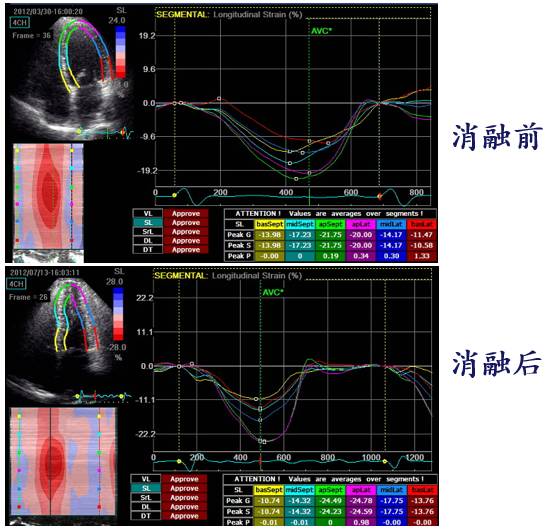

HFpEF + 房颤 导管消融

心室率控制

随访

◆消融后心功能正常,阵发房扑

◆3年后因阵发房扑行第二次消融

◆随访9年

SHFM 消融前(上)后(下)

[19]